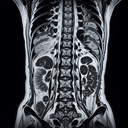

МРТ поперекового крижового відділу хребта

МРТ поперекового-крижового відділу хребта— це неінвазивне дослідження, яке використовує магнітні поля та радіохвилі для отримання детальних зображень хребта. Воно дозволяє виявити різноманітні патології, такі як грижі міжхребцевих дисків, здавлення нервових корінців, дегенеративні зміни, пухлини та запальні процеси. **Переваги MРТ:** - Висока якість зображень, що забезпечує детальну оцінку тканин...